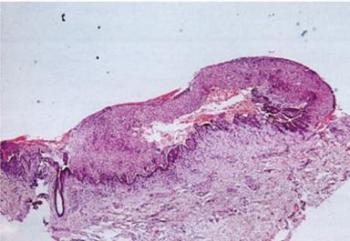

1.9. ábra. Intraepithelialis bullaképződés a szájnyálkahártyán

(J.A. Regezi, J.J. Sciubba, R.C.K.Jordan. Oral Patholgy, Saunders, Elsevier, St. Louis. 2008)